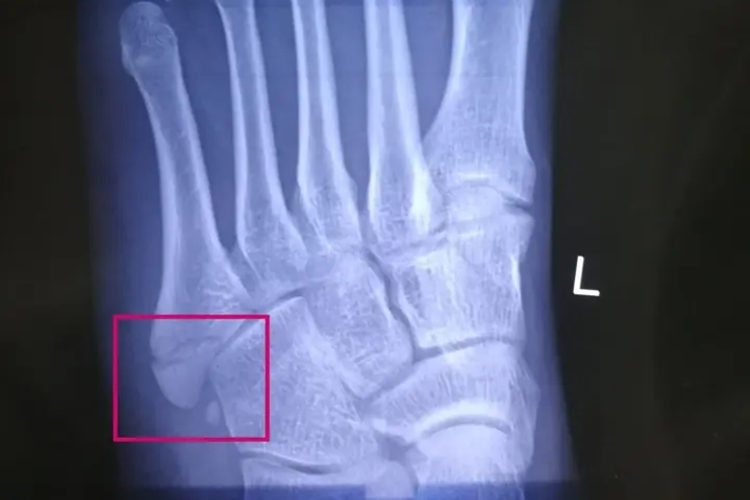

第五跖骨骨折即骨的完整性和连续性遭到破坏,多位于第五跖骨基底部,常表现为累及区域的触痛、肿胀、行走受限等,急性损伤者局部可见淤斑,X线显示一条类似的透亮线将骨折片与第五跖骨分离,且骨折形态多样,如横行、斜行。